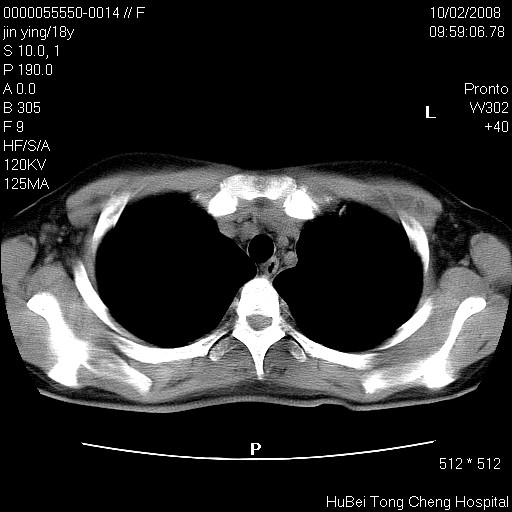

患者 女,18y。发热十余天,伴咳嗽。pe:t39⒈℃,bp 110/80mmhg,p 86次/min。神清,精神欠佳。双肺可闻及少许湿罗音。既往史不详。

临床诊断:肺部感染?

胸部ct轴位平扫(层厚10mm,螺距1.5,重建间隔10mm),图像如下: